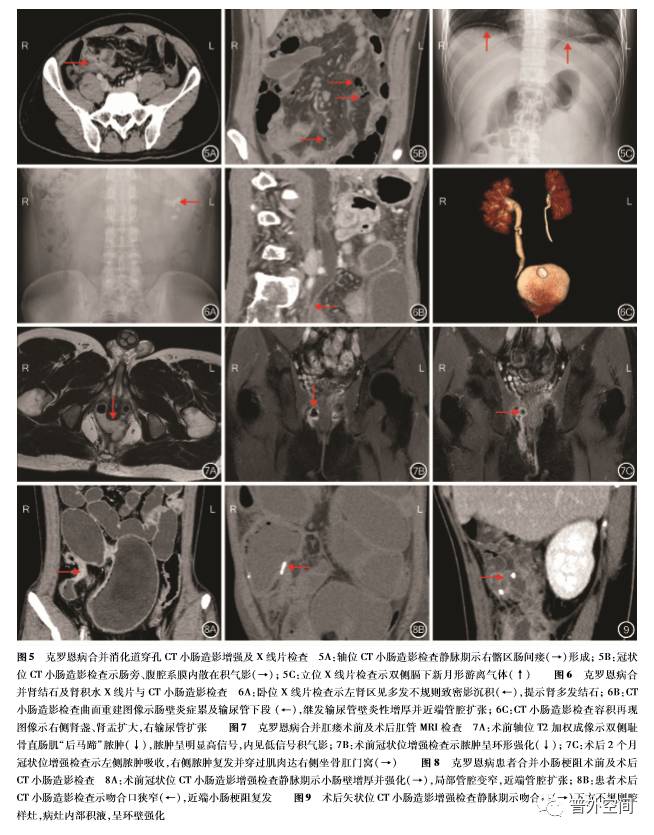

2. 3. 5 肠穿孔:3例患者合并消化道穿孔,其中1 例同时合并肠瘘。CTE和 X线片检查示肠旁系膜 或腹腔膈下出现游离气体影。见图5。

2. 3. 6 肾结石和肾积水: 2例患者分别合并肾结石 和肾积水。肾结石 X线检查示肾盏内多发边缘锐 利的致密影沉积,肾积水CTE检查示输尿管壁炎性 增厚并近端管腔扩张,肾盂肾盏积水。见图6。

128例患者均成功行手术治疗及获得随访,随 访时间为4~2 7个月。1 0例患者因术后并发症再 次手术, 7例肛瘘复发,肛管MRI检查示既往病变部 位的瘘管或脓肿愈合不全或进展,病灶形态及位置 与术前大致相仿。2例吻合口狭窄CTE检查示肠壁 增厚,吻合口近端梗阻扩张。1例吻合口瘘 CTE增 强检查示金属吻合环旁不规则腔样灶,病灶内部积液,可见边缘强化。见图7~9。其余118例患者术 后恢复良好,CTE或 MRE检查未见肠瘘、肠梗阻并 发症。

针对克罗恩病合并的各种并发症,CTE、MRE 检查及肛管 MRI检查都具有鲜明的影像学特点。 肛瘘或肛周脓肿是克罗恩病常见的并发症,其具体 发生的机制尚不明确[2 1]。克罗恩病肛瘘往往比较 复杂,与常见的隐窝腺性感染形成的瘘管有着明显 的不同,其表现为多个内口、多条瘘管、多发脓肿的 高位复杂型肛瘘,有时难以用传统的 Pa r k′ s分型具 体地划分。本研究中有9 2%的患者发生复杂性肛 瘘。肛管MRI检查能多维度观察内口方位、主瘘管 及分支瘘管走行以及脓肿的大小位置。肛瘘影像学 表现为多条管道状走行的异常信号,瘘管呈明显较 均匀强化或管壁强化、管腔无强化,这与管腔内的成 分是肉芽肿或是脓液相关。肛瘘合并脓肿可发生在 肛周间隙,同样能发生在括约肌内,其部位不一、形 态多样,例如坐骨肛门窝脓肿表现为类圆形,耻骨直 肠肌脓肿表现为后马蹄形;由于内部脓液较多,T2 加权及弥散加权成像脓肿呈明显高信号,增强呈环 形强化,内部无强化。由于克罗恩病为肠壁全层透 壁性炎,炎症穿透肠壁深入系膜,产生窦道或肠管与 其他器官粘连形成通道时,就会出现肠瘘。肠瘘可 累及邻近的任何器官,形成肠 肠瘘、肠 膀胱瘘、肠 阴道瘘、肠 腹壁瘘等。肠内瘘相对外瘘更加常见, 其中肠间瘘最多见,表现肠管之间相互粘连、分界不 清,多段肠管花瓣样聚集,形成“星征”[1 0]。此外, 由于肠壁炎症长期、反复的刺激,可引起肠壁细胞外 基质成分发生改变,炎症细胞及纤维组织增多,从而 并发肠管狭窄,继发肠梗阻。肠梗阻表现为肠壁增 厚狭窄并异常强化,近端肠管扩张积液;增厚肠壁根 据病理成分的不同可分为纤维性或炎性狭窄,这在 T2加权图像信号、肠壁强化及其他功能成像上会有 不同的影像表现。腹腔脓肿在克罗恩病患者中也不 少见,其往往和肠瘘共同发生。脓肿可发生在腹部 的任何位置,包括系膜内、腹膜后、膈下、肠壁内、腹 壁内等。克罗恩病合并腹腔脓肿表现为系膜内、腹 壁、膈下或其他部位出现椭圆形或圆形的包块,周围 炎性渗出,脓肿壁出现强化。急性穿孔的直接征象 是肠壁出现缺损或瘘口,这在克罗恩病中很少出现, 本研究中影像学医师依据膈下或系膜旁出现游离气体的间接征象提示肠穿孔的诊断。克罗恩病除继发 肠道并发症外,亦可出现其他系统的肠外并发症,如 胆结石、门静脉血栓、硬化性胆管炎、肾结石、肾积 水、骨关节炎、虹膜炎、皮肤结节性红斑、坏疽性脓皮 病等[1 5]。本研究主要探讨肠道并发症,缺乏对肠外 并发症的研究,仅2例肠外表现患者亦合并有肠道 并发症。术后复发或二次并发症的患者,影像学表 现与术前基本类似。